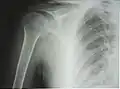

Рентгенограмма верхней части плечевой кости с выраженной хирургической шейкой

Проксимальный эпифиз представлен головкой плечевой кости (лат. caput humeri), отделённой от диафиза анатомической шейкой (лат. collum anatomicum). Головка сочленяется с суставной впадиной лопатки, образуя плечевой сустав. За шейкой располагаются два бугорка (апофиза) — больший и меньший (лат. tuberculum majus et minus), между которыми проходит межбугорковая бороздка — место сухожилия длинной головки двуглавой мышцы плеча. Ниже бугорков, на границе с диафизом, проходит хирургическая шейка (лат. collum chirurgicum) — место наиболее частых переломов плечевой кости[3].

К 4—6 годам указанные центры сливаются в единую головку плечевой кости. Замещение метаэпифизарного хряща на границе проксимального эпифиза и диафиза костной тканью (синостоз) наступает в подростковом возрасте, благодаря чему продолжается рост кости в длину. На рентгенограмме ребёнка или подростка определяется характерный светлый участок на месте метаэпифизарного хряща, который может быть принят за перелом или трещину[4].